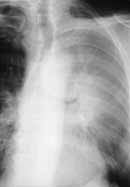

Рентгенологическая оценка эффективности химиолучевой терапии МКРЛ представляет определенные трудности. Изменения в бронхах и легких (постлучевой фиброз, трансформация легочного рисунка, деформация бронхов и т. д.), связанные с облучением искажают истинную динамику процесса. В связи с этим часто не удается определить, произошла ли полная регрессия опухоли на фоне постлучевых изменений или имеются остаточные явления опухолевого поражения (Рис. 2). В таких случаях более определенную картину может дать только повторное компьютерное исследование.

Рис. 2. Рак левого верхнедолевого бронха. (а) Обзорная рентгенограмма в прямой проекции до лечения.

Рис. 2. Рак левого верхнедолевого бронха. (б) Обзорная рентгенограмма в прямой проекции после химиолучевого лечения (постлучевой пульмонит, фиброз).